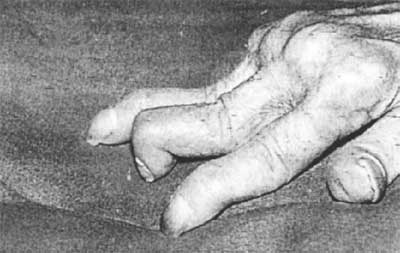

صور توضح التشوهات المفصلية في مريض الروماتويد

يعتبر مرض الروماتويد المفصلي( التهاب المفاصل الشبه روماتيزمي) أحد أمراض المناعة الذاتية الذي لا يعرف حتى الآن سببا محددا لحدوثه، ويعد الروماتويد المفصلي مثالا للمرض المزمن الذي يصيب الجسم بالتشوه ويؤثر على العديد من مفاصله بصورة متماثله متبعا في ذلك مسارا طويلا ومترددا على شكل فترات من السكون وأخرى من التفاقم ومؤثرا على المفاصل الصغيرة الطرفية.

هو مرض التهابي مزمن يصيب معظم المفاصل كما يصيب أجهزة أخرى ويعتبر أحد الأمراض المناعية الذاتية. ويعد مرض الروماتويد أكثر الأمراض الروماتيزمية انتشاراً بعد الفُصال العظمي (خشونة المفاصل). كما أنه أكثرها شدةً وألماً حيث أنه يؤدي إلى تدمير وتشوه المفاصل إذا لم يُعالج مبكراً. وهو يصيب الجنسين ولكنه لدى النساء أكثر بنسبة 1:3 عنه في الرجال ، ويتركز مابين الخامسة والثلاثين والخمسين من العمر إلا أنه يصيب أي مرحلة عمرية من الطفولة إلى الشيخوخة.

يبدأ الروماتويد عند حوالي ثلثي المرضى تقريباً بشكل مفاجئ مع شعور بالتعب والإرهاق وضعف عام بما في ذلك الضعف الجنسي. أما الأعراض الخاصة فإنها تظهر عادة بشكل تدريجي بحيث تصيب مفاصل متعددة وخصوصاً مفاصل اليدين والمعصم والركبة والقدمين أو أي مفاصل أخرى وتكون الإصابة متناظرة. وتتركز الأعراض في المفاصل على شكل آلام وتورم في المفاصل مصحوبة بتيبس صباحي ، وعادة ما تظهر هذه الأعراض بشكل تدريجي. أما تأثيره على أجزاء الجسم الأخرى فتحدث لدى نسبة مختلفة من المرضى ، ويتمثل في ظهور عقد تحت الجلد ، جفاف في العينين أو الفم وربما التهاب في أجزاء من العين، التهاب الغشاء البلوري للرئة وتليف في نسيج الرئة ، التهاب الغشاء المحيط بالقلب (التامور) والتهاب في الأوعية الدموية والأعصاب الطرفية ،وفي حالة تأثيره على فقرات الرقبة قد يؤثر على الحبل الشوكي.